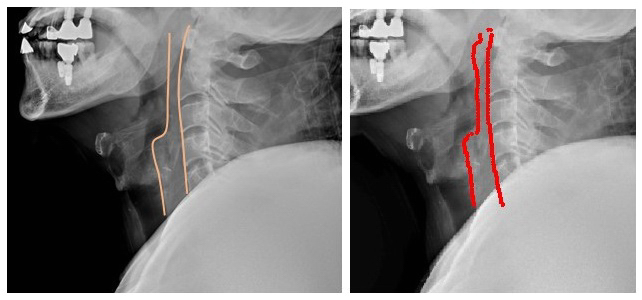

실제 치과 보철치료를 받은 외상환자의 경추 X-ray 영상을 영상의학과 의사가 판독한 결과와 AI가 판독한 결과를 비교했을 때 큰 차이를 보이지 않았다. 엑스레이를 판독할 때 척추 앞 공간을 보기 위해 척추 앞 공간선을 그리게 되는데 AI 역시 의사가 그린 공간선과 같은 모양을 그렸다.